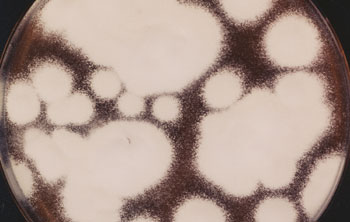

Fuß- und Nagelpilzerkrankungen werden überwiegend durch Fadenpilze (Dermatophyten) wie Trichophyton rubrum und Trichophyton mentagrophites verursacht (Letzterer hier im Bild). Für die Überlassung des Bildes und Zustimmung zur Veröffentlichung dankt die Redaktion dem mykologischen Labor der Universitäts-Hautklinik Düsseldorf und deren früherem Direktor Professor Dr. Dr. Thomas Ruzicka. |

Nagelpilz entwickelt sich häufig aus einer nicht oder nicht ausreichend behandelten Fußpilzerkrankung, da er im Wesentlichen durch die gleichen Erreger verursacht wird. Dies sind überwiegend Dermatophyten, insbesondere Trichophyton rubrum und Trichophyton mentagrophites, der neuerdings auch Trichophyton interdigitale genannt wird (Abbildung).